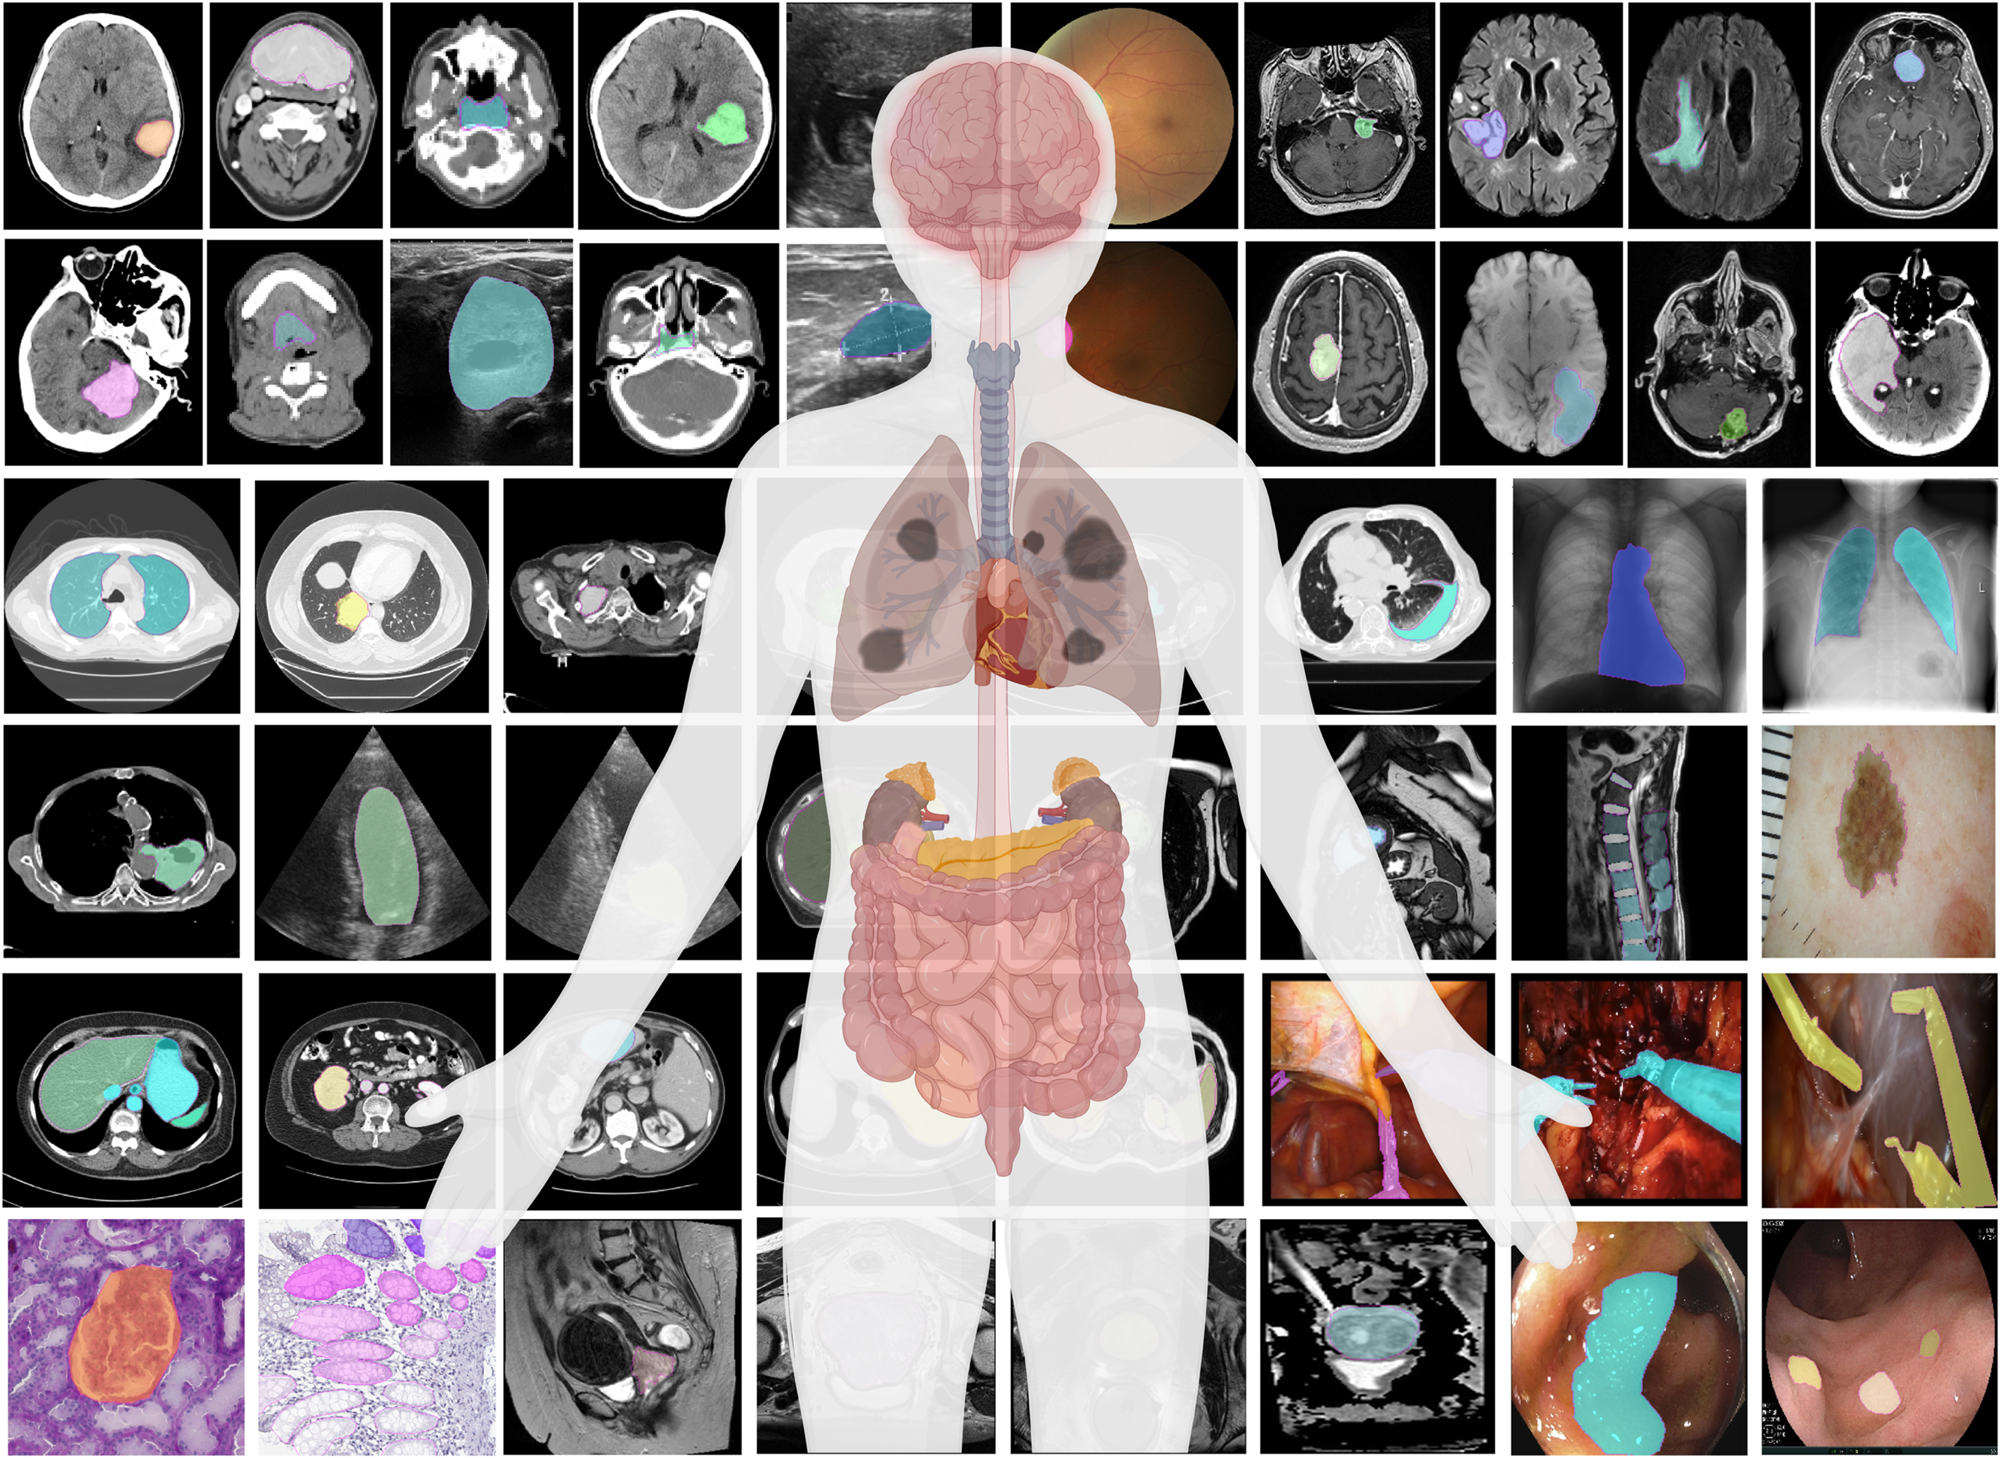

Computer Vision: Medical Applications

Detection and segmentation are the most impactful CV tasks in medicine:

- Nodule detection in chest CT / lung scans

- Cell counting in microscopy images

- Polyp detection in colonoscopy

- Surgical instrument tracking in robotic surgery

- Fracture detection in skeletal X-rays

- Organ segmentation for surgical planning and volume measurement

- Tumor delineation for radiation treatment planning and growth monitoring

- Cell segmentation in microscopy for counting and morphology analysis

- Tissue type differentiation (gray/white matter, cerebrospinal fluid in brain MRI)

- Vessel segmentation for angiography analysis

Segmentation is the most detailed form of visual understanding — it classifies every pixel in an image. Instead of one label per image (classification) or boxes around objects (detection), segmentation produces a mask that precisely outlines each region of interest. This matters clinically: a bounding box around a tumor tells you roughly where it is, but a segmentation mask tells you its exact shape, volume, and boundaries — critical for surgical planning and radiation therapy.